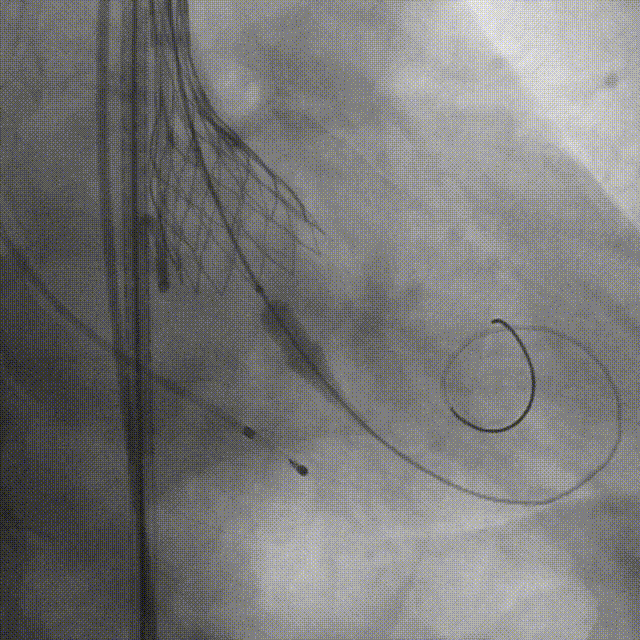

导丝跨瓣

瓣膜定位,0位释放

释放2/3处造影确认植入深度

释放瓣膜